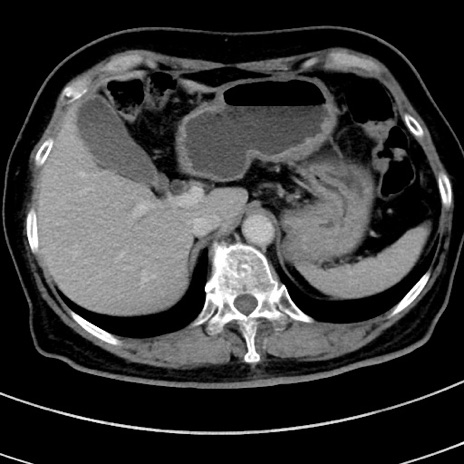

症例9(横断像)

【症例】 60歳代女性

【主訴】むかつき、みぞおちの痛み

【現病歴】3日前よりむかつきがあり、食事がとれない。

【既往歴】糖尿病

【身体所見】発熱なし、心窩部圧痛軽度あるも、腹膜刺激症状なし。

【データ】WBC 7400、CRP 1.92